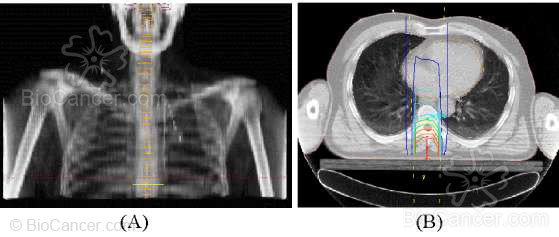

Figura 2. Tratamiento con radioterapia de una compresión medular. (A) Reconstrucción radiográfica digital. (B) Curvas de isodosis.

Habitualmente se utiliza radioterapia con fraccionamientos altos: 5 sesiones de 400 cGy ó 10 sesiones de 300 cGy, con el fin de disminuir rápidamente la masa tumoral. En los casos en que se espere mayor supervivencia se puede emplear el fraccionamiento convencional de 200 cGy/día administrando una dosis total de 40 Gy. La respuesta a la radiación es buena, con mejoría del dolor en el 75% de los enfermos. Si el paciente estaba parapléjico antes de comenzar el tratamiento es difícil que vuelva a caminar. Son factores de buen pronóstico para la recuperación neurológica del paciente la progresión lenta de los síntomas, el no tener instaurada la paraplejia ni la incontinencia de esfínteres antes de comenzar la irradiación y el que se trate de un tumor radiosensible. Normalmente no se presentan efectos agudos importantes secundarios a la irradiación. La supervivencia dependerá fundamentalmente de la evolución del tumor primario.